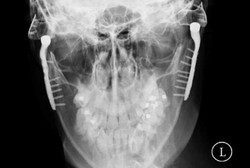

Setelah membantu memulihkan wajah seorang pria yang 'berantakan' karena kecelakaan motor, kini lagi-lagi printer 3D telah membantu kasus kesehatan lainnya. Seorang balita yang berhasil diselamatkan nyawanya setelah mampu membantu balita tersebut bernapas.